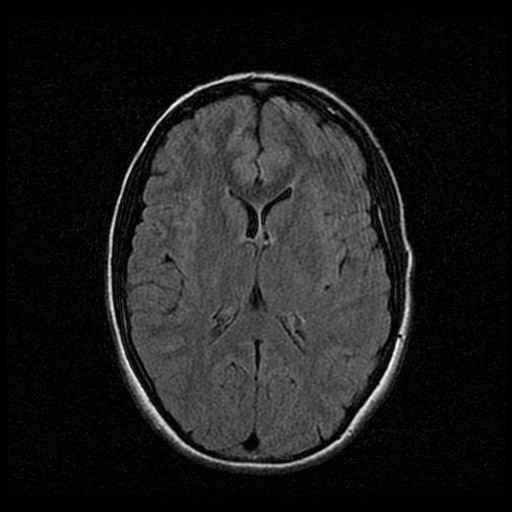

Schedel